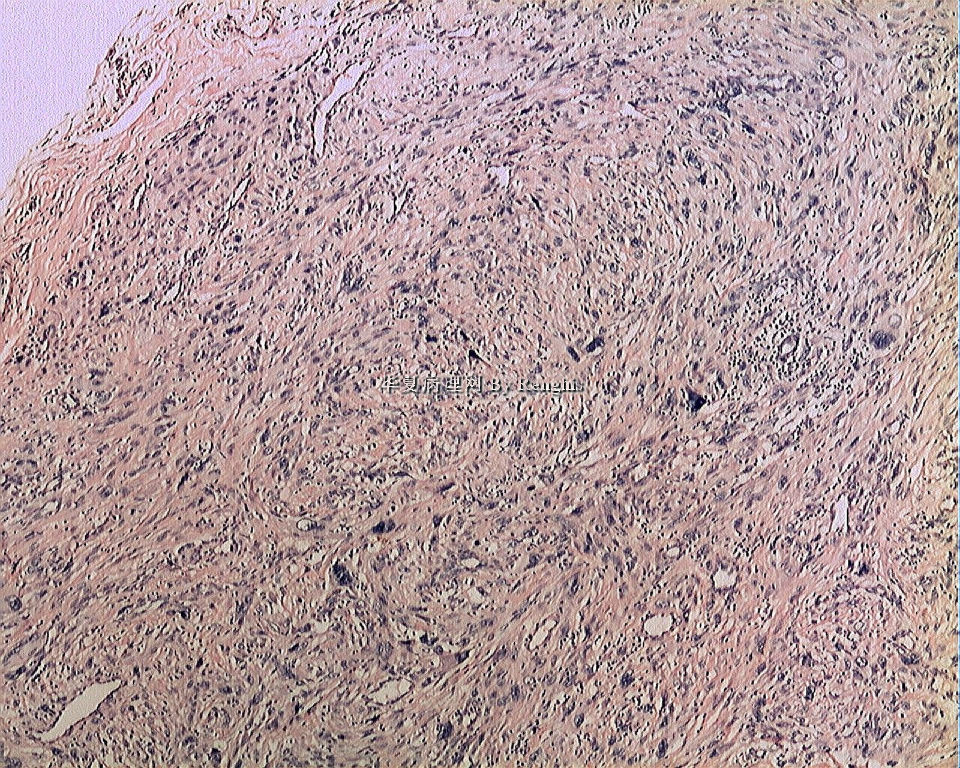

女,29岁,左大腿内侧肿物直径2.8cm,切面灰白、实性、质中,似有包膜。

本人认同此例是一例比较典型的纤维肉瘤,瘤细胞程束状、鱼骨状及编织状排列,部分瘤细胞异型性明显,免疫组化vimentin阳性,SMA灶状弱阳性,desmin阴性,S100阴性,CK阴性,EMA阴性,余记不得了,明天看看再上传。